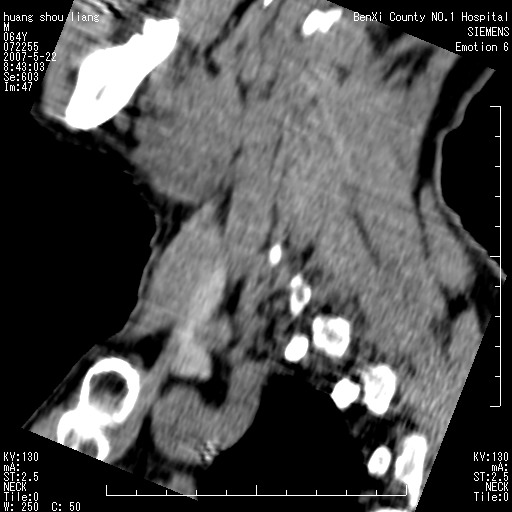

标题: CT8337:颈部包块8年,颈部CT和VRT,请讨论。

男性,64岁。颈部包块8年。最近增大。

对不起大家,可能是片子发太多有点乱,正常腮腺在下颌角的外侧,颌下腺在下颌体的中部内侧,本例在下颌角内侧偏下,和腺体一点关系都没有,从vrt和mpr上可以很明显看出来,再者肿块是好多粘连在一块的,大家在仔细看看,左侧可能也是吧,我还是考虑为肿大的淋巴结融合在一块,但性质??????

右侧腮腺下部均匀软组织密度肿块,外形不规则,与周围组织分界清晰,考虑右侧腮腺混合瘤或多形性腺瘤。

大家好,病理结果出来了,如大家所说,颌下腺混合瘤。

唉,解剖没学好吧,我诊断错了,不过还是有些不理解回去我在多看看书,谢谢大家的参与,以后我还会奉献好的病例。